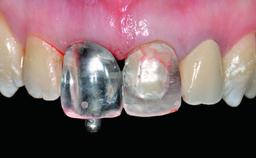

Replacement of a Missing Upper Left Central Incisor: Late Placement of an RC Bone Level Implant, CAD/CAM Zirconia Abutment

| Abutment Type | CAD/CAM |

| Prosthesis Type | FDP |

| Retention | Cemented, with prosthesis margin < 3mm submucosal Cemented, with prosthesis margin < 3mm submucosal |

| Provisional Implant-Supported Prosthesis | Prosthodontic margin > 3 mm apical to mucosal margin Prosthodontic margin > 3 mm apical to mucosal margin |